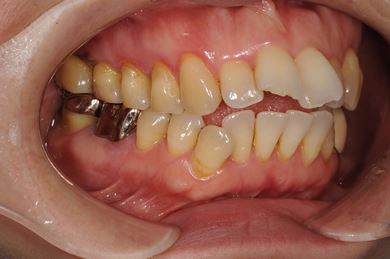

インプラントの症例写真 IMPLANT

インプラント治療+ソケットリフト+GBR

| 性別/年齢 | 女性 / 55歳 | ||||||||||||||||||||||||||||||||

| 主訴 | 奥歯が3本抜歯されてしまったあとにインプラントを入れたい。 | ||||||||||||||||||||||||||||||||

| 治療内容 | インプラント3本(ソケットリフト、GBR)、ハイブリッドセラミック3本 | ||||||||||||||||||||||||||||||||

| 総治療費 | 1,295,300円 | ||||||||||||||||||||||||||||||||

| 治療期間 | 8ヶ月 |